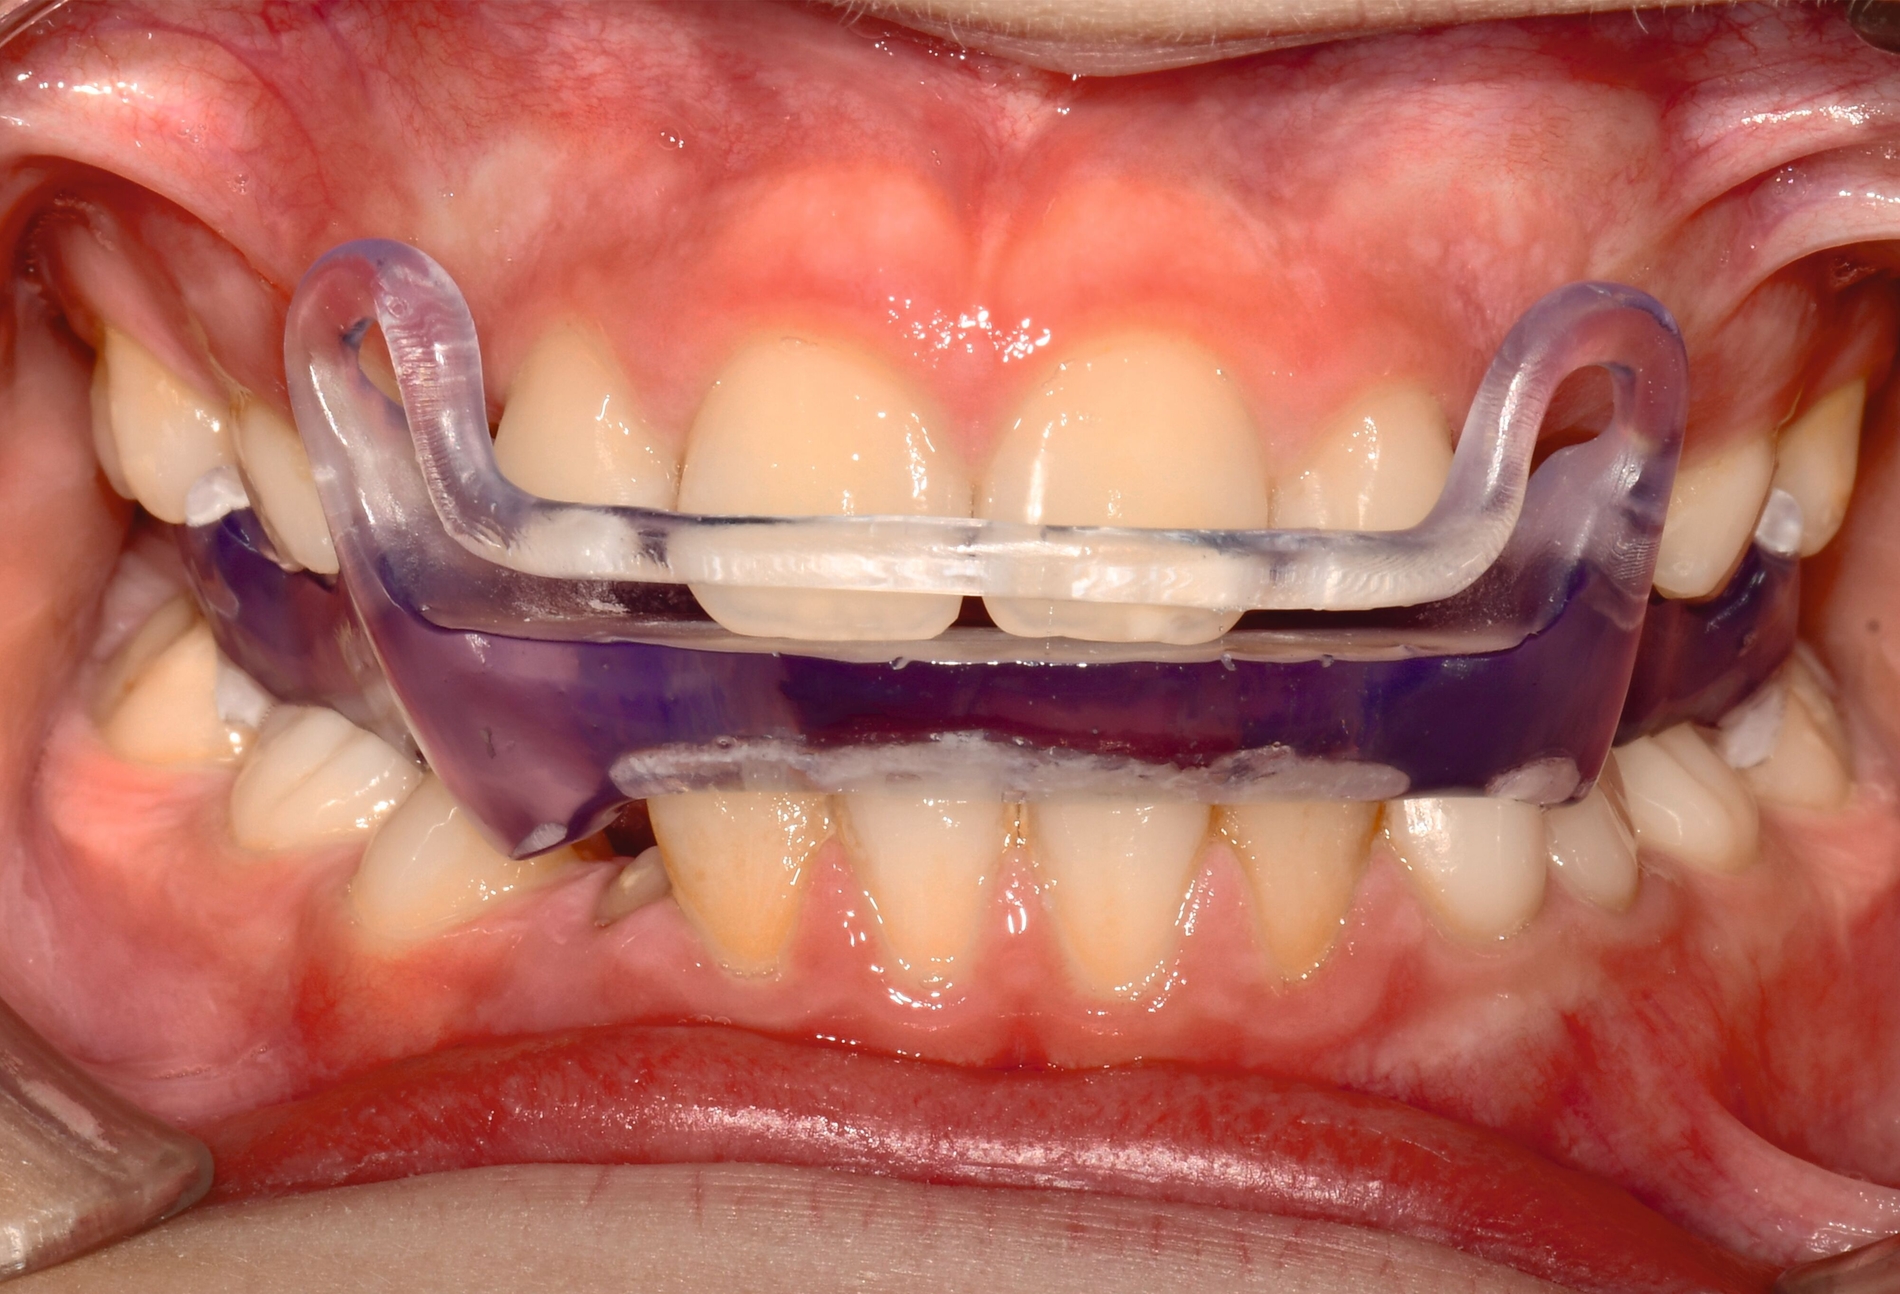

Herausnehmbare Apparaturen

Als hochinnovatives Feld hat sich auch die Herstellung herausnehmbarer Apparaturen im 3-D-Druck entwickelt (Abbildung 4), beschränkt sich jedoch noch auf einzelne Forschungsansätze [Al Mortadi et al., 2012; van der Meer et al., 2016; Graf et al., 2022; Keller et al., 2022]. Intensiv an neuen Konzepten in der Herstellung 3-D-gedruckter herausnehmbarer Apparaturen wird am Universitätsklinikum Heidelberg geforscht. Da herausnehmbare kieferorthopädische Apparaturen im Regelfall bei jungen Patienten eingesetzt werden, kommt dem Vorteil einer unbegrenzten Replikation und einer kostengünstigen und schnelleren Herstellung ein besonderer Stellenwert zu.

Im Unterschied zu konventionellen Apparaturen bestehen die 3-D-gedruckten Apparaturen vollkommen aus Kunststoff. Eine Einarbeitung metallischer Elemente nach dem 3-D-Druck ist möglich [Al Mortadi et al., 2012; Al Mortadi et al., 2024], erfordert jedoch zusätzlichen Zeitaufwand. Zur Herstellung herausnehmbarer Apparaturen eignen sich konventionelle praxisinterne 3-D-Stereolithografie-Drucker, die in vielen Fällen bereits im regulären Praxisalltag zum Modelldruck verwendet werden. Die verwendeten Kunststoffe sollten dabei eine Klasse-IIa-Zertifizierung aufweisen, so dass ein sicherer langfristiger intraoraler Einsatz der Apparatur gewährleistet ist. Weiter muss die Apparatur nach dem 3-D-Druck gemäß den Herstellerangaben nachprozessiert werden. Im Regelfall beinhaltet dieser Prozess ein Waschen in Isopropylalkohol (IPA) sowie eine Nachhärtung im Lichthärtegerät. Eigens durchgeführte Studien sowie die bisherige klinische Erfahrung bestätigen eine hohe mechanische Stabilität, eine hohe Passgenauigkeit sowie eine breite Akzeptanz der Patienten [Roser et al., 2021; Roser et al., 2023; Segnini et al., 2023]. Des Weiteren wecken die 3-D-gedruckten Apparaturen bei den meist jungen Patienten großes Interesse, was wiederum die Trage-Compliance unterstützt. Durch weitere Entwicklungen im 3-D-Druckbereich wird zukünftig auch ein Farbdruck möglich werden.